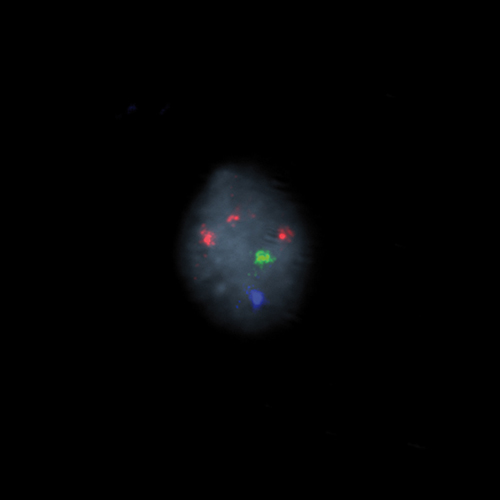

Hybridization of the RCAN1 (21q22), SE X, SE Y probe to a male metaphase spread showing normal pattern (2R1G1B)

IVD RCAN1/SE X/SE Y

RCAN1 (21q22), SE X, SE Y